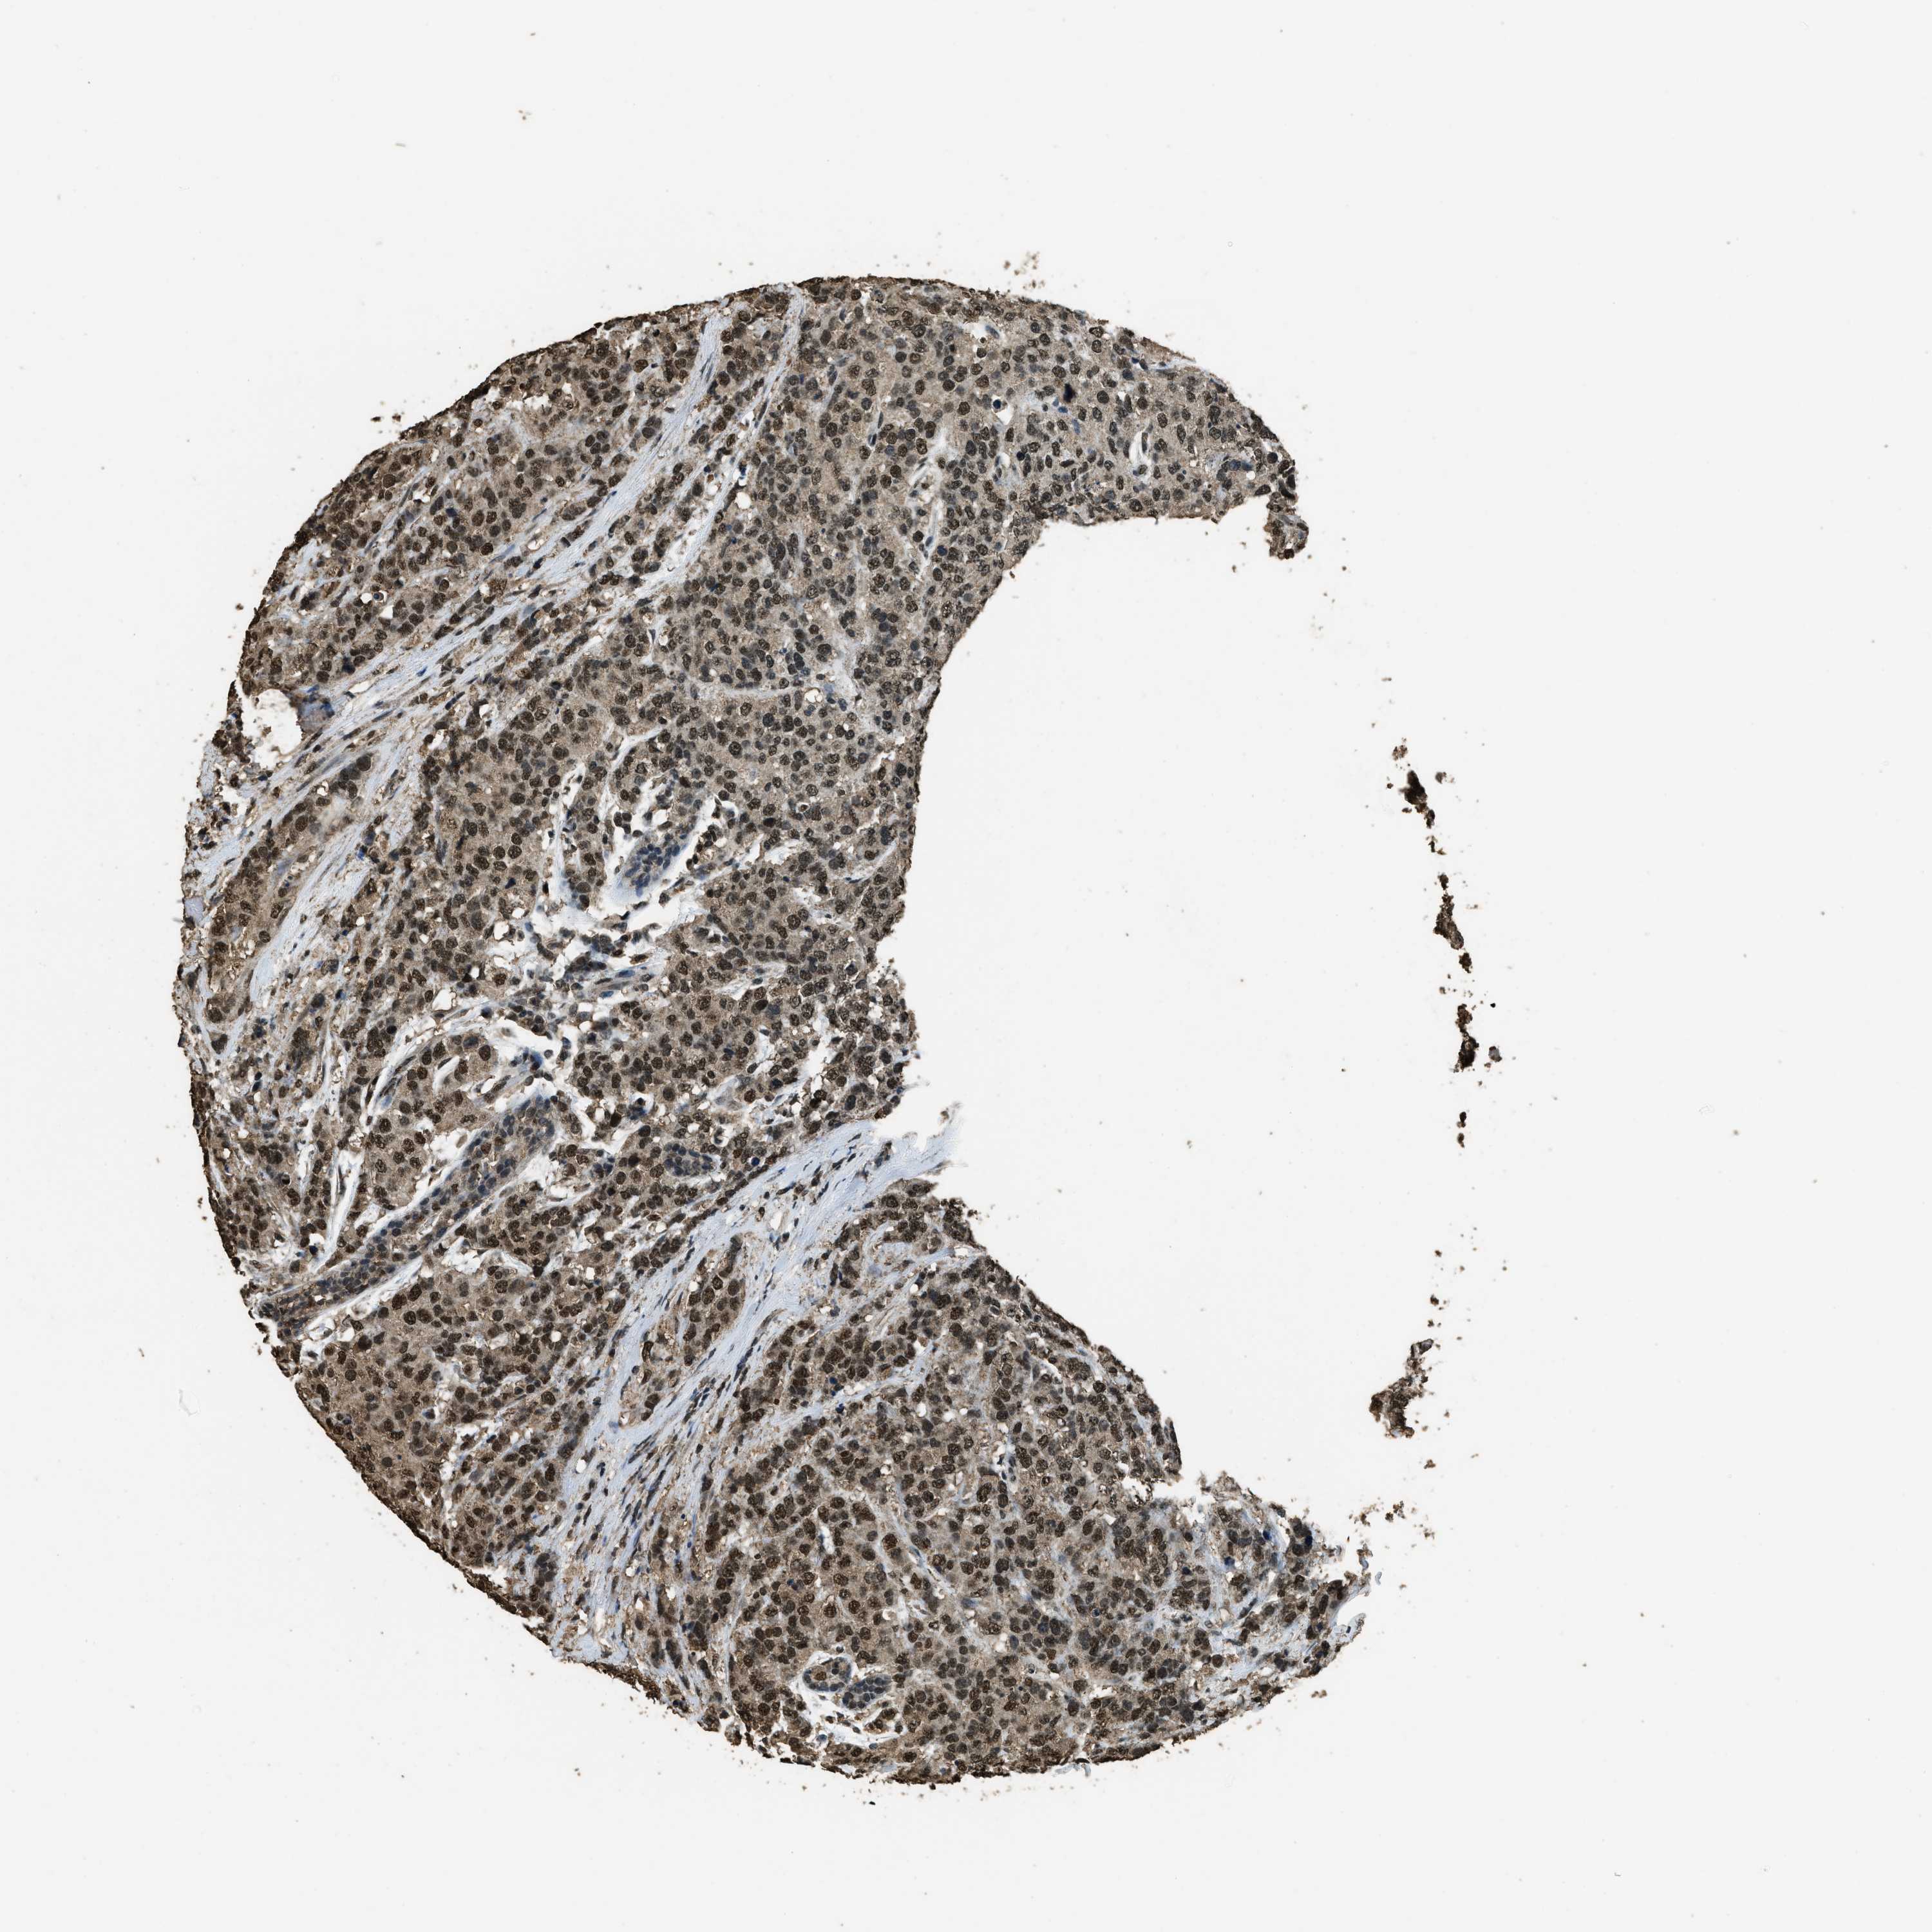

CANCER BREAST CANCER Show tissue menu

BRCA TCGA BRCA VALIDATION PROTEIN EXPRESSION